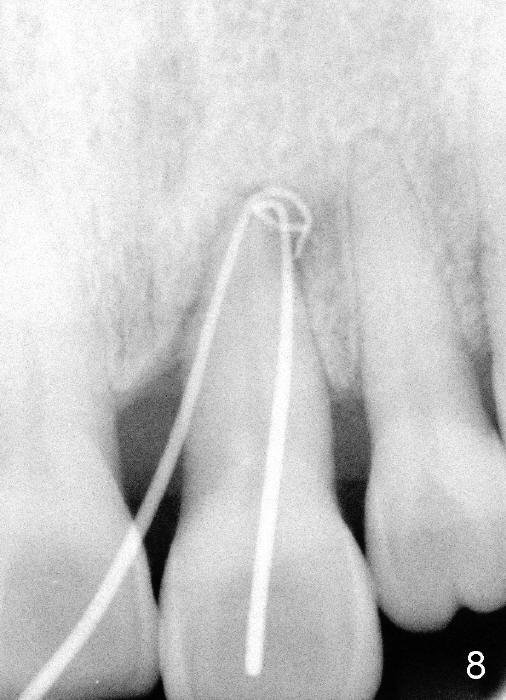

A 60-year-old lady had an abscess mesial to #9 six years ago (Fig.1,2 <), treated as a perio lesion by laser (Fig.3) and osseous surgery without bone graft (Fig.6, followed by CT exam revealing semi-circumferential bone loss (Fig.4,5). When the perio treatment failed, attention was paid to endo aspect (Fig.7-9). In fact the pulp was found to be vital when access to root canal therapy was made. As expected, the treatment failed again. The palatal fistula persisted. The infection was suspected to be a source of remote immediate implant site (#30). The tooth #9 was extracted. It appears that there is a semilunar crack line in the linguomesial root (Fig.12). When the socket healed 2 weeks post extraction (Fig.10), the #30 buccal defect was debrided with bone graft. There was no bone resorption 4 weeks post extraction (Fig.11); a 4.5x17 mm implant was placed (Fig.13-15). An immediate provisional was fabricated (Fig.16-18). Fig.19,20 were taken 3 months post implantation and 7 months post cementation, respectively. Dense bone forms around the implant coronally 4 years 5 months post cementation (Fig.21), while the gingiva is healthy palatally (Fig.22) and buccally (Fig.23).